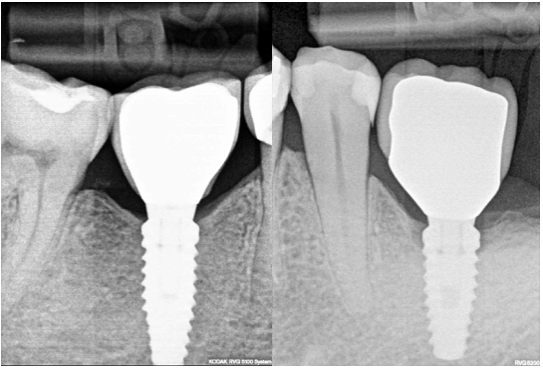

On the other hand, let’s admit, that all of us would choose Fig 1 A implant, without bone loss, and not Fig 1B implant, although the difference is very small. Sometimes clinicians tend to downplay this bone loss because simply they do not understand, why the bone is disappearing, and are not eager to learn.